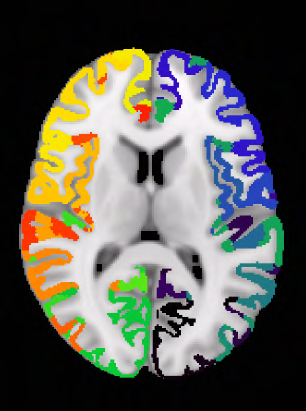

Our knowledge of the organisation of the human brain at the population-level is yet to translate into power to predict functional differences at the individual-level, limiting clinical applications, and casting doubt on the generalisability of inferred mechanisms. It remains unknown whether the difficulty arises from the absence of individuating biological patterns within the brain, or from limited power to access them with the models and compute at our disposal. Here we comprehensively investigate the resolvability of such patterns with data and compute at unprecedented scale. Across 23 810 unique participants from UK Biobank, we systematically evaluate the predictability of 25 individual biological characteristics, from all available combinations of structural and functional neuroimaging data. Over 4526 GPU hours of computation, we train, optimize, and evaluate out-of-sample 700 individual predictive models, including fully-connected feed-forward neural networks of demographic, psychological, serological, chronic disease, and functional connectivity characteristics, and both uni- and multi-modal 3D convolutional neural network models of macro- and micro-structural brain imaging. We find a marked discrepancy between the high predictability of sex (balanced accuracy 99.7%), age (mean absolute error 2.048 years, R2 0.859), and weight (mean absolute error 2.609Kg, R2 0.625), for which we set new state-of-the-art performance, and the surprisingly low predictability of other characteristics. Neither structural nor functional imaging predicted psychology better than the coincidence of chronic disease (p<0.05). Serology predicted chronic disease (p<0.05) and was best predicted by it (p<0.001), followed by structural neuroimaging (p<0.05). Our findings suggest either more informative imaging or more powerful models are needed to decipher individual level characteristics from the human brain.